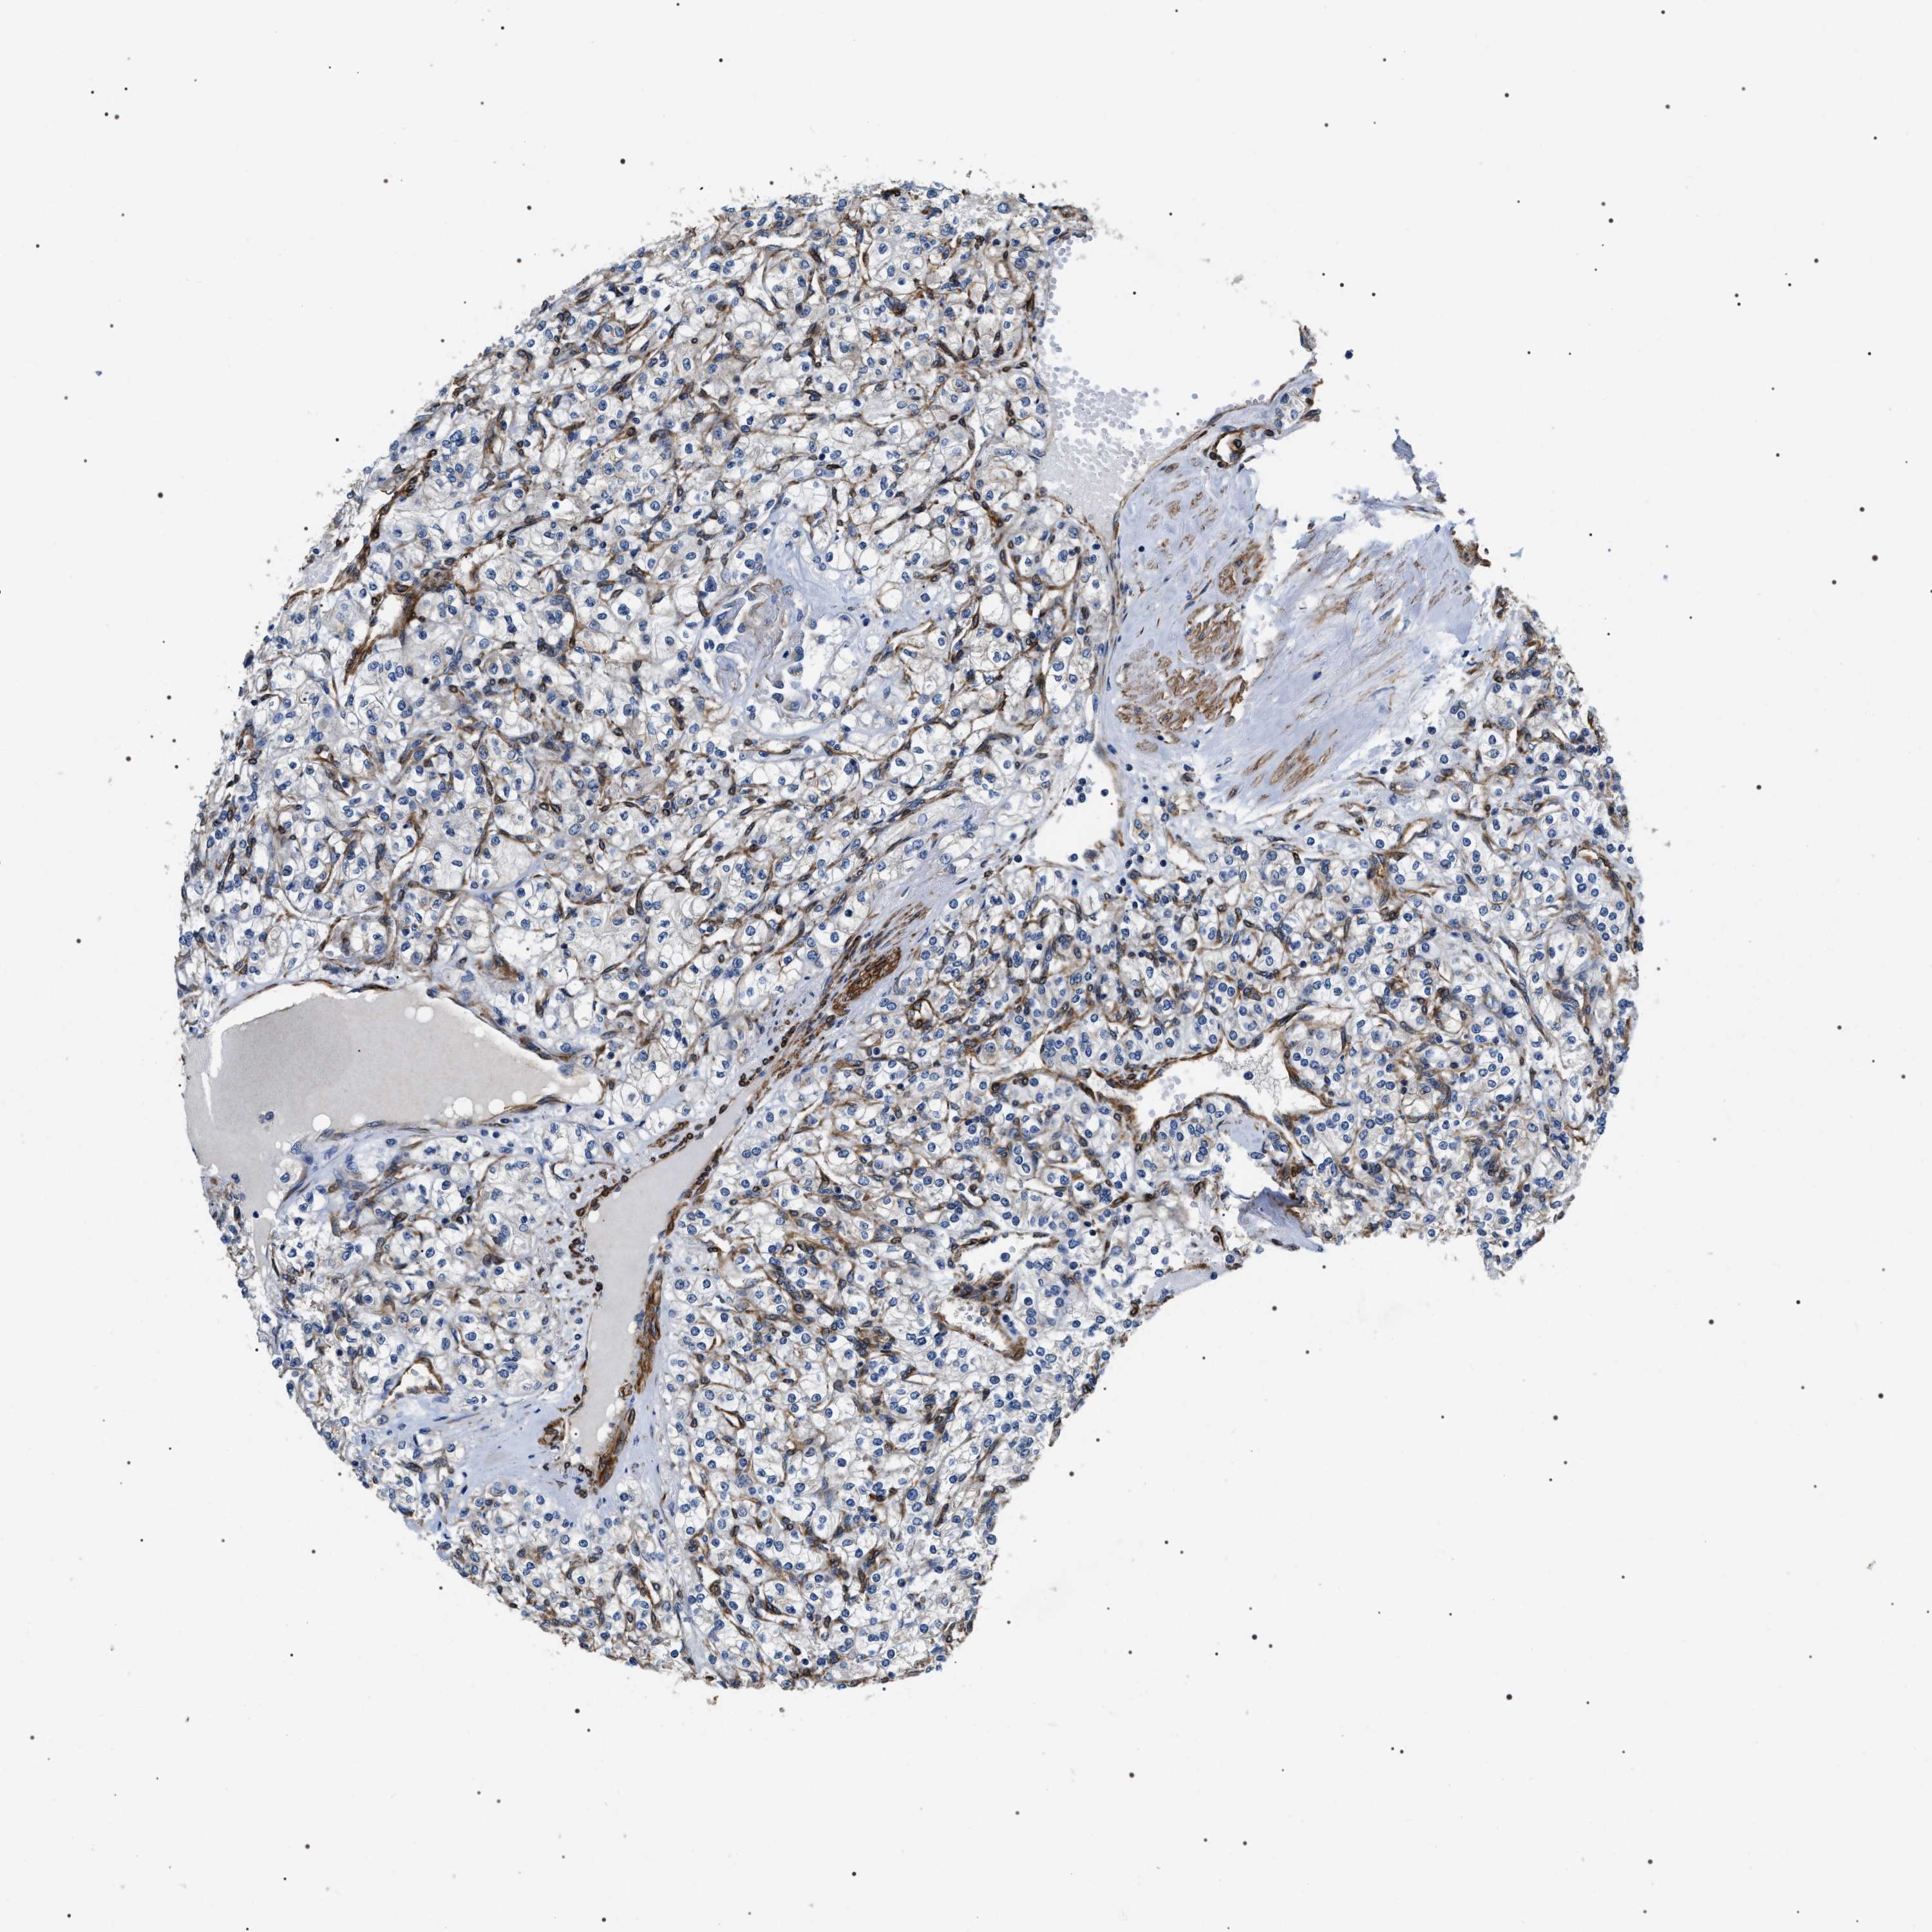

KIDNEY RENAL CLEAR CELL CARCINOMA (TCGA) - Interactive survival scatter ploti

The Survival Scatter plot shows the clinical status (i.e. dead or alive) for all individuals in the patient cohort, based on the same data that underlies the corresponding Kaplan-Meier plots. Patients that are alive at last time for follow-up are shown in blue and patients who have died during the study are shown in red.

The x-axis shows the expression levels (FPKM) of the investigated gene in the tumor tissue at the time of diagnosis. The y-axis shows the follow-up time after diagnosis (years). Both axes are complimented with kernel density curves demonstrating the data density over the axes. The top density plot shows the expression levels (FPKM) distribution among dead (red) and alive patients (blue). The right density plot shows the data density of the survived years of dead patients with high and low expression levels respectively, stratified using the cutoff indicated by the vertical dashed line through the Survival Scatter plot. This cutoff is automatically defined based on the FPKM cutoff that minimizes the p-score. The cutoff can be changed by dragging the vertical line or by entering a cutoff value in the square labeled "Current cut-off".

Under the Survival Scatter plot the p-score landscape (black curve; left axis) is shown together with dead median separation (red curve; right axis). Dead median separation is the difference in median mRNA expression between patients who have died with high and low expression, respectively. It is calculated as follows: median FPKM expression of dead patients with high expression - median FPKM expression of dead patients with low expression. This is intended to aid the user in visually exploring custom cutoffs and the associated p-scores and dead median separation.

Individual patient data is displayed and can be filtered by clicking on one or more of the category buttons on the top of the page. Categories describing expression level and patient information include: high, low, alive, dead, female, male and tumor stages. The scale of the x-axis can be toggled between linear and log-scale by clicking on the "x log" button. Mouse-over function shows TCGA ID, patient information and mRNA expression (FPKM) for each patient.

& Survival analysisi

Kaplan-Meier plots summarize results from analysis of correlation between mRNA expression level and patient survival. Patients were divided based on level of expression into one of the two groups "low" (under cut off) or "high" (over cut off). X-axis shows time for survival (years) and y-axis shows the probability of survival, where 1.0 corresponds to 100 percent.

ZC3HAV1L is not prognostic in Kidney Renal Clear Cell Carcinoma (TCGA)

: 9.88

N/A

Average pTPM 7.1

Number of samples 521